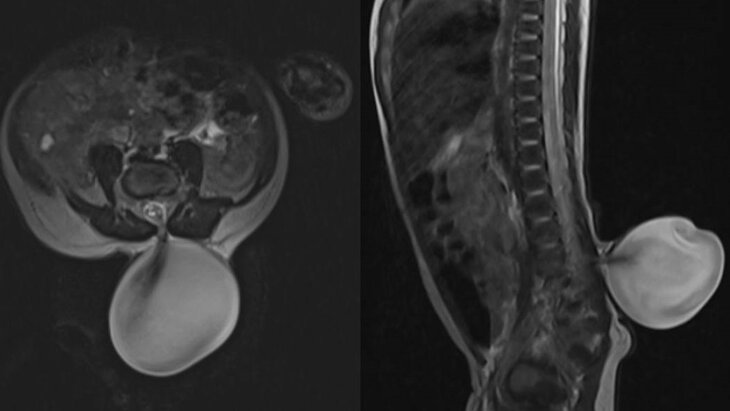

По итогам магнитно-резонансной томографии врачи диагностировали малышу "менингомиелоцеле" – грыжу спинномозгового канала, при которой происходит выпячивание тканей и вещества спинного мозга через костный дефект позвоночного столба.

В ведомстве отметили, что выявленная грыжа могла привести к серьезному ослаблению силы мышц ног юного пациента. С учетом высокого риска неврологических осложнений медики приняли решение о проведении операции.

В ходе хирургического вмешательства, продолжительность которого составила два часа, специалисты аккуратно отделили спинной мозг от грыжевого мешка и восстановили нормальную анатомию позвоночного канала. Процедура прошла успешно и не вызвала осложнений у ребенка.